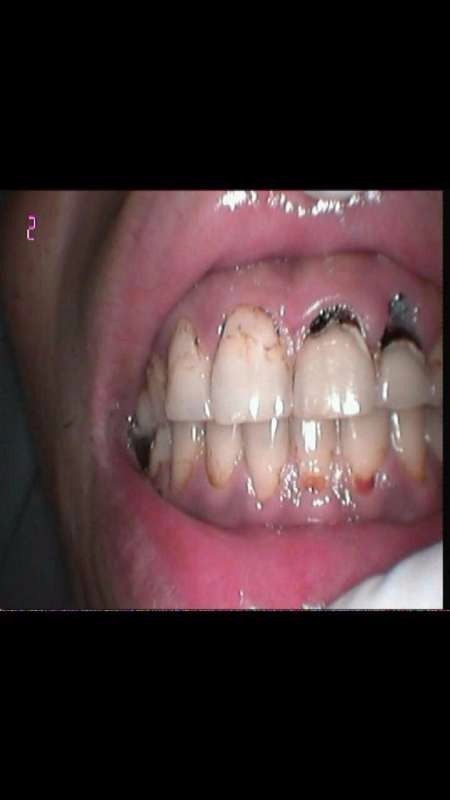

前牙颈部龋坏

2122号牙颈部龋坏达髓腔,叩痛,无松动

右上牙颈部龋坏